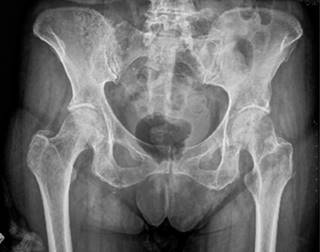

Podemos realizar una primera aproximación diagnóstica solicitando una radiografía de pelvis, con proyecciones anteroposteriores y axiales, por su facilidad y coste a la hora de realizarse. Comúnmente, evidenciaremos esclerosis subcondral, irregularidad de la sínfisis y resorción ósea, en casos avanzados (Figura 1).8 La prueba que mayor información nos va a aportar será la resonancia magnética (RM). Será frecuente encontrarse un edema medular difuso, el cual se extiende desde la superficie subcondral, que a menudo involucra ambas ramas púbicas.9 Además, se suelen encontrar signos de periostitis, irregularidades de las superficiales articulares, erosiones, osteofitos anteriores y posteriores y quistes subcondrales. El signo de la herradura está comúnmente presente (Figura 2). Las uniones miotendinosas se conservan, a menos que haya tendinopatía coexistente.9